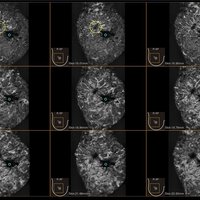

Das IBUS 60 ist ein intelligentes Brust-Vollvolumen-Ultraschallsystem der Marke SIUI.

Das IBUS 60 zeichnet sich durch Sicherheit und Komfort aus. Es bietet ein hochauflösendes Bild und reduziert somit Fehldiagnosen, was ideal für die Brustuntersuchung ist, insbesondere bei einer dichten Brust.

• Dreidimensionale Positionierung

• Nanopure Technologie zur Specklereduzierung